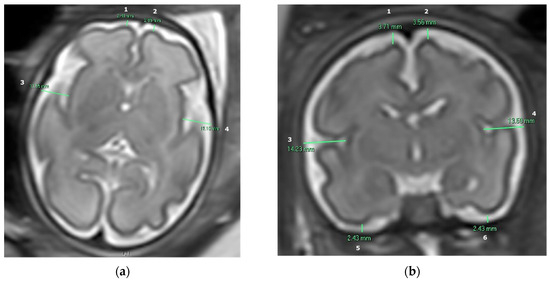

The subarachnoid space width was measured in MR images in both axial and coronal planes in ten specific anatomical locations. Measurements were conducted manually in 2D slices using the Carestream Vue PACS system, width measured in millimeters. We obtained four measurements in the axial plane: the right and left frontal gyri and the right and left insula gyri. We also obtained six measurements in the coronal plane: the right and left frontal gyri, the right and left insula gyri, and the right and left inferior temporal gyri, as presented by Figure 1.

As previously explained, measurements of the subarachnoid space were collected in ten specific anatomical locations—four in the axial plane and six in the coronal plane (presented in Figure 1)—and two analyses were conducted: one between the macrocephaly and microcephaly groups, and another between the microcephaly and FGR groups.

Figure 1. T2-weighted fetal brain MR image demonstrating the measurements of the subarachnoid space in millimeters: (a) Axial plane: (1) Right frontal gyrus. (2) Left frontal gyrus. (3) Right insula gyrus. (4) Left insula gyrus. (b) Coronal plane: (1) Right frontal gyrus. (2) Left frontal gyrus. (3) Right insula gyrus. (4) Left insula gyrus. (5) Right inferior temporal gyrus. (6) Left inferior temporal gyrus.